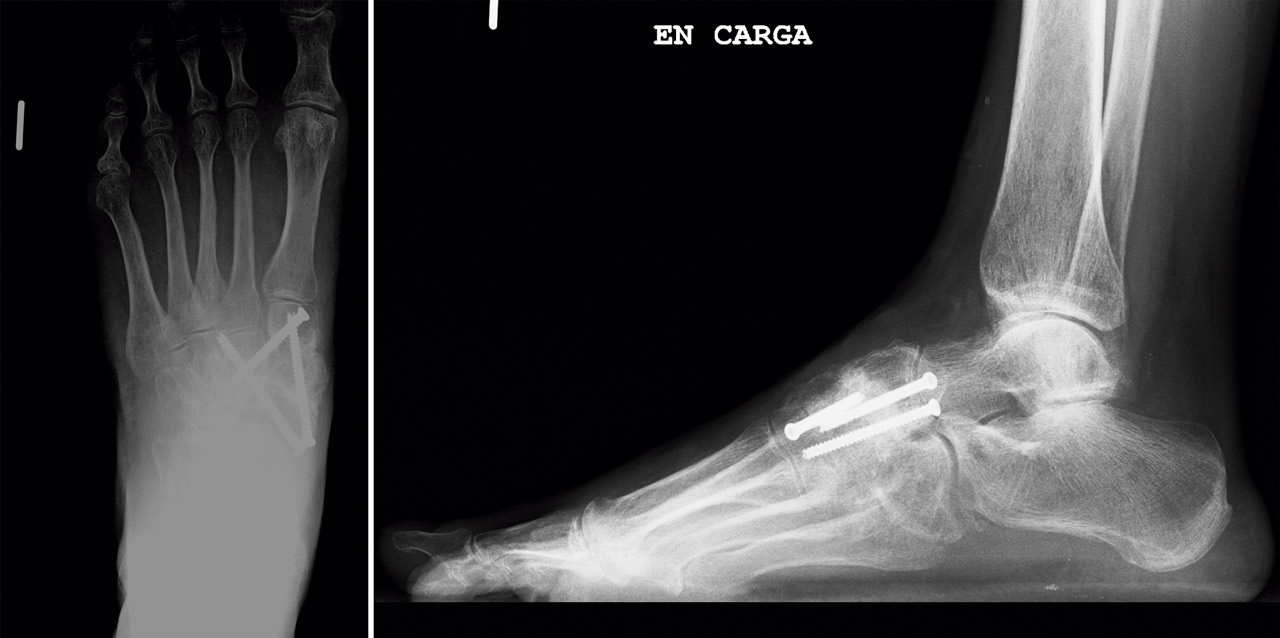

En el postoperatorio, la paciente llevó una inmovilización con férula de yeso las 2 primeras semanas y una bota de yeso durante 4 semanas más. A partir de las 6 semanas se le autorizó la carga con una ortesis de tipo Rom Walker®. A los 3 meses se comprobó la consolidación con el estudio radiológico (Figura 6), retirándose la ortesis, y se inició el tratamiento rehabilitador. Tras un periodo de 8 semanas de tratamiento fisioterápico, la paciente se recuperó satisfactoriamente y volvió a realizar sus actividades normales sin molestias.

Figura 6. Estudio radiológico a los 3 meses.